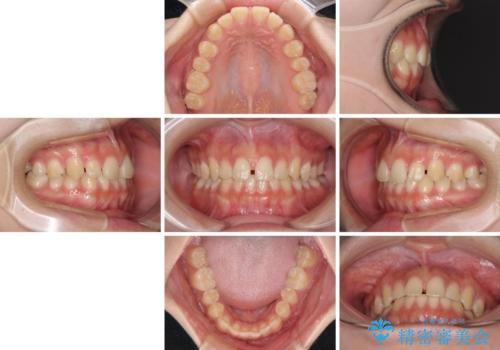

- 上顎前歯の隙間を気にして来院された患者様です。

目立たない装置を希望とのことで、インビザラインを用いて矯正治療を行うこととしました。

一度インビザラインのマウスピースセットをお渡しすると1年以上来院されず、マウスピースを破損したり紛失したりすると来院されるというのんびりとしたペースで治療を行ったため、4年間という長期にわたる治療となりました。

最終的には隙間は全て閉じ、綺麗な仕上がりとなりました。